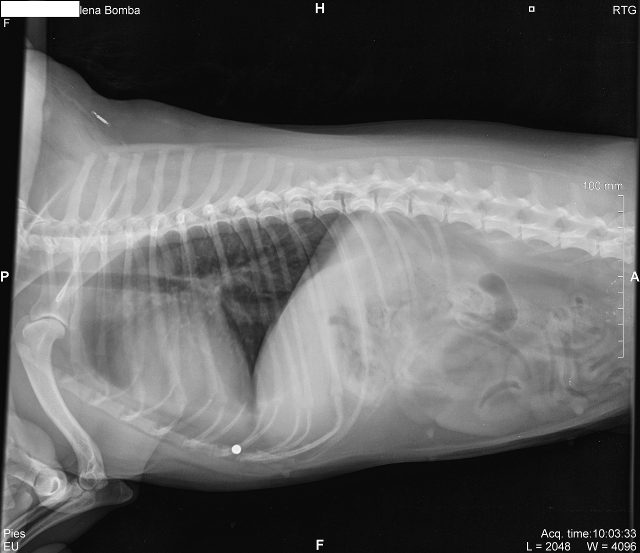

Owca ma kłopoty... :( (Spróbuję po kolei.) Kilka m-cy temu zauważyłam, że jakoś często zdarza się Owcy, że w czasie wycierania łap (pozycja leżąca na boku albo na plecach) delikatnie próbować mnie łapać ząbkami za rękę, jakby chciała ją odsunąć. Wcześniej zdarzało się to bardzo sporadycznie. Wtedy praktycznie po każdym spacerze. Poszłyśmy do weta, który obmacał brzuch, boczki, stawy i nic nie stwierdził. Potem jakoś samo znowu przeszło i tylko znów zdarzało się sporadycznie. Pod koniec listopada wróciło. I tak miałam iść do weta podciąć owcze wilcze pazury, więc 29.11 poszłam i znów zapytałam o to "odganianie ręki". Obmacanie znów nic nie dało... Ale w ciągu tygodnia objawów przybywało: - wrzask w czasie czesania pleców, jakbym ze skóry obdarła (uznałam, że pociągnęłam za mocno albo drapnęłam, bo jak czesałam dalej, to nic się nie działo); - dużo dłuższe namyślanie się na skok na moją kanapę (po wyproszonym pozwoleniu komendą "hop"), na niższą kanapę inkówny wskakuje bez namysłu; - zero proszenia o rzucanie piłki na porannych spacerach (od początku jesieni czasem jej się zdarzało, że nie miała chęci ganiać, ale wtedy kładłam to na karb pogorszonej kondycji po kilku tygodniach pobytu w Otwocku, gdzie możliwości ganiania bez smyczy ma ograniczone), przez cały tamten tydzień to była tak z 1-2 min. biegania ze znalezionym samodzielnie patykiem, a w zeszłym tygodniu 3 małe kółka wokół ukochanego Borysa i z minuta zaczepiania nas do zabawy; - nadwrażliwość skóry na grzbiecie w kilku wydaniach (poszukiwanie urazu skóry nic nie dawało): * taki odruchowy skurcz mięśni jakby bólowy przypominający odganianie much przez krowę, gdy głaskałam ją, jak odprężona leżała ze mną na kanapie, * próby drapania się lub gryzienia w grzbiet, gdy np. dotknęła ja tam lużna (lekka, cienka) taśma smyczy automatycznej, * próby ugryzienia własnego ogona, gdy ten dotknął ją do grzbietu w czasie merdania i radosnego zwijania się w precelek na powitanie, - kilka razy miałam wrażenie, że koo robi na dwie tury, jakby nie mogła za długo ustać "w kucki"... 05.12 ponownie poszłam z nią do weta. Opisałam objawy, zastanawiając się, czy nie zostanę uznana za jakąś neurotyczkę. Wet obmacał Owcę kojelny raz ze szczególnym uwzględnieniem kręgosłupa. Urazów nie wykrył, ale reakcję bólową tak. Podejrzenie zwyrodnienia. Zalecił RTG. Byliśmy dziś. Wynik: Obraz kręgosłupa w normie wiekowej. W okolicy mostkowej cień śruciny. Tak, RTG nie wykazał zmian w kościach, co nie wyklucza jednak zwyrodnienia, np. chrząstek. Jakiś stan zapalny z pewnością jest, skoro jest reakcja nadwrażliwości. Już nasz wet zalecił lek p/zapalno-p/bólowy na tydzień (Carprodyl F 20mg). Jak zadziała, to mamy powtarzać w przypadku powrotu objawów. Jak nie zadziała, to dalsze poszukiwania źródła problemu, czyli rezonans magnetyczny (wolę chwilowo nie sprawdzać ceny...). Wolimy, żeby zadziałał. Prosimy o kciuki. Śrut w okolicy mostka nie sprawia problemów i nie ma w tej chwili wskazania do jego usunięcia. Uwaga! Czarny humor! Nooo, wiedzieliśmy, że Owca jest postrzelona ;), ale nie sądziliśmy, że dosłownie... :/ Ewa Marta, bardzo Ci dziękuję za wsparcie. <3